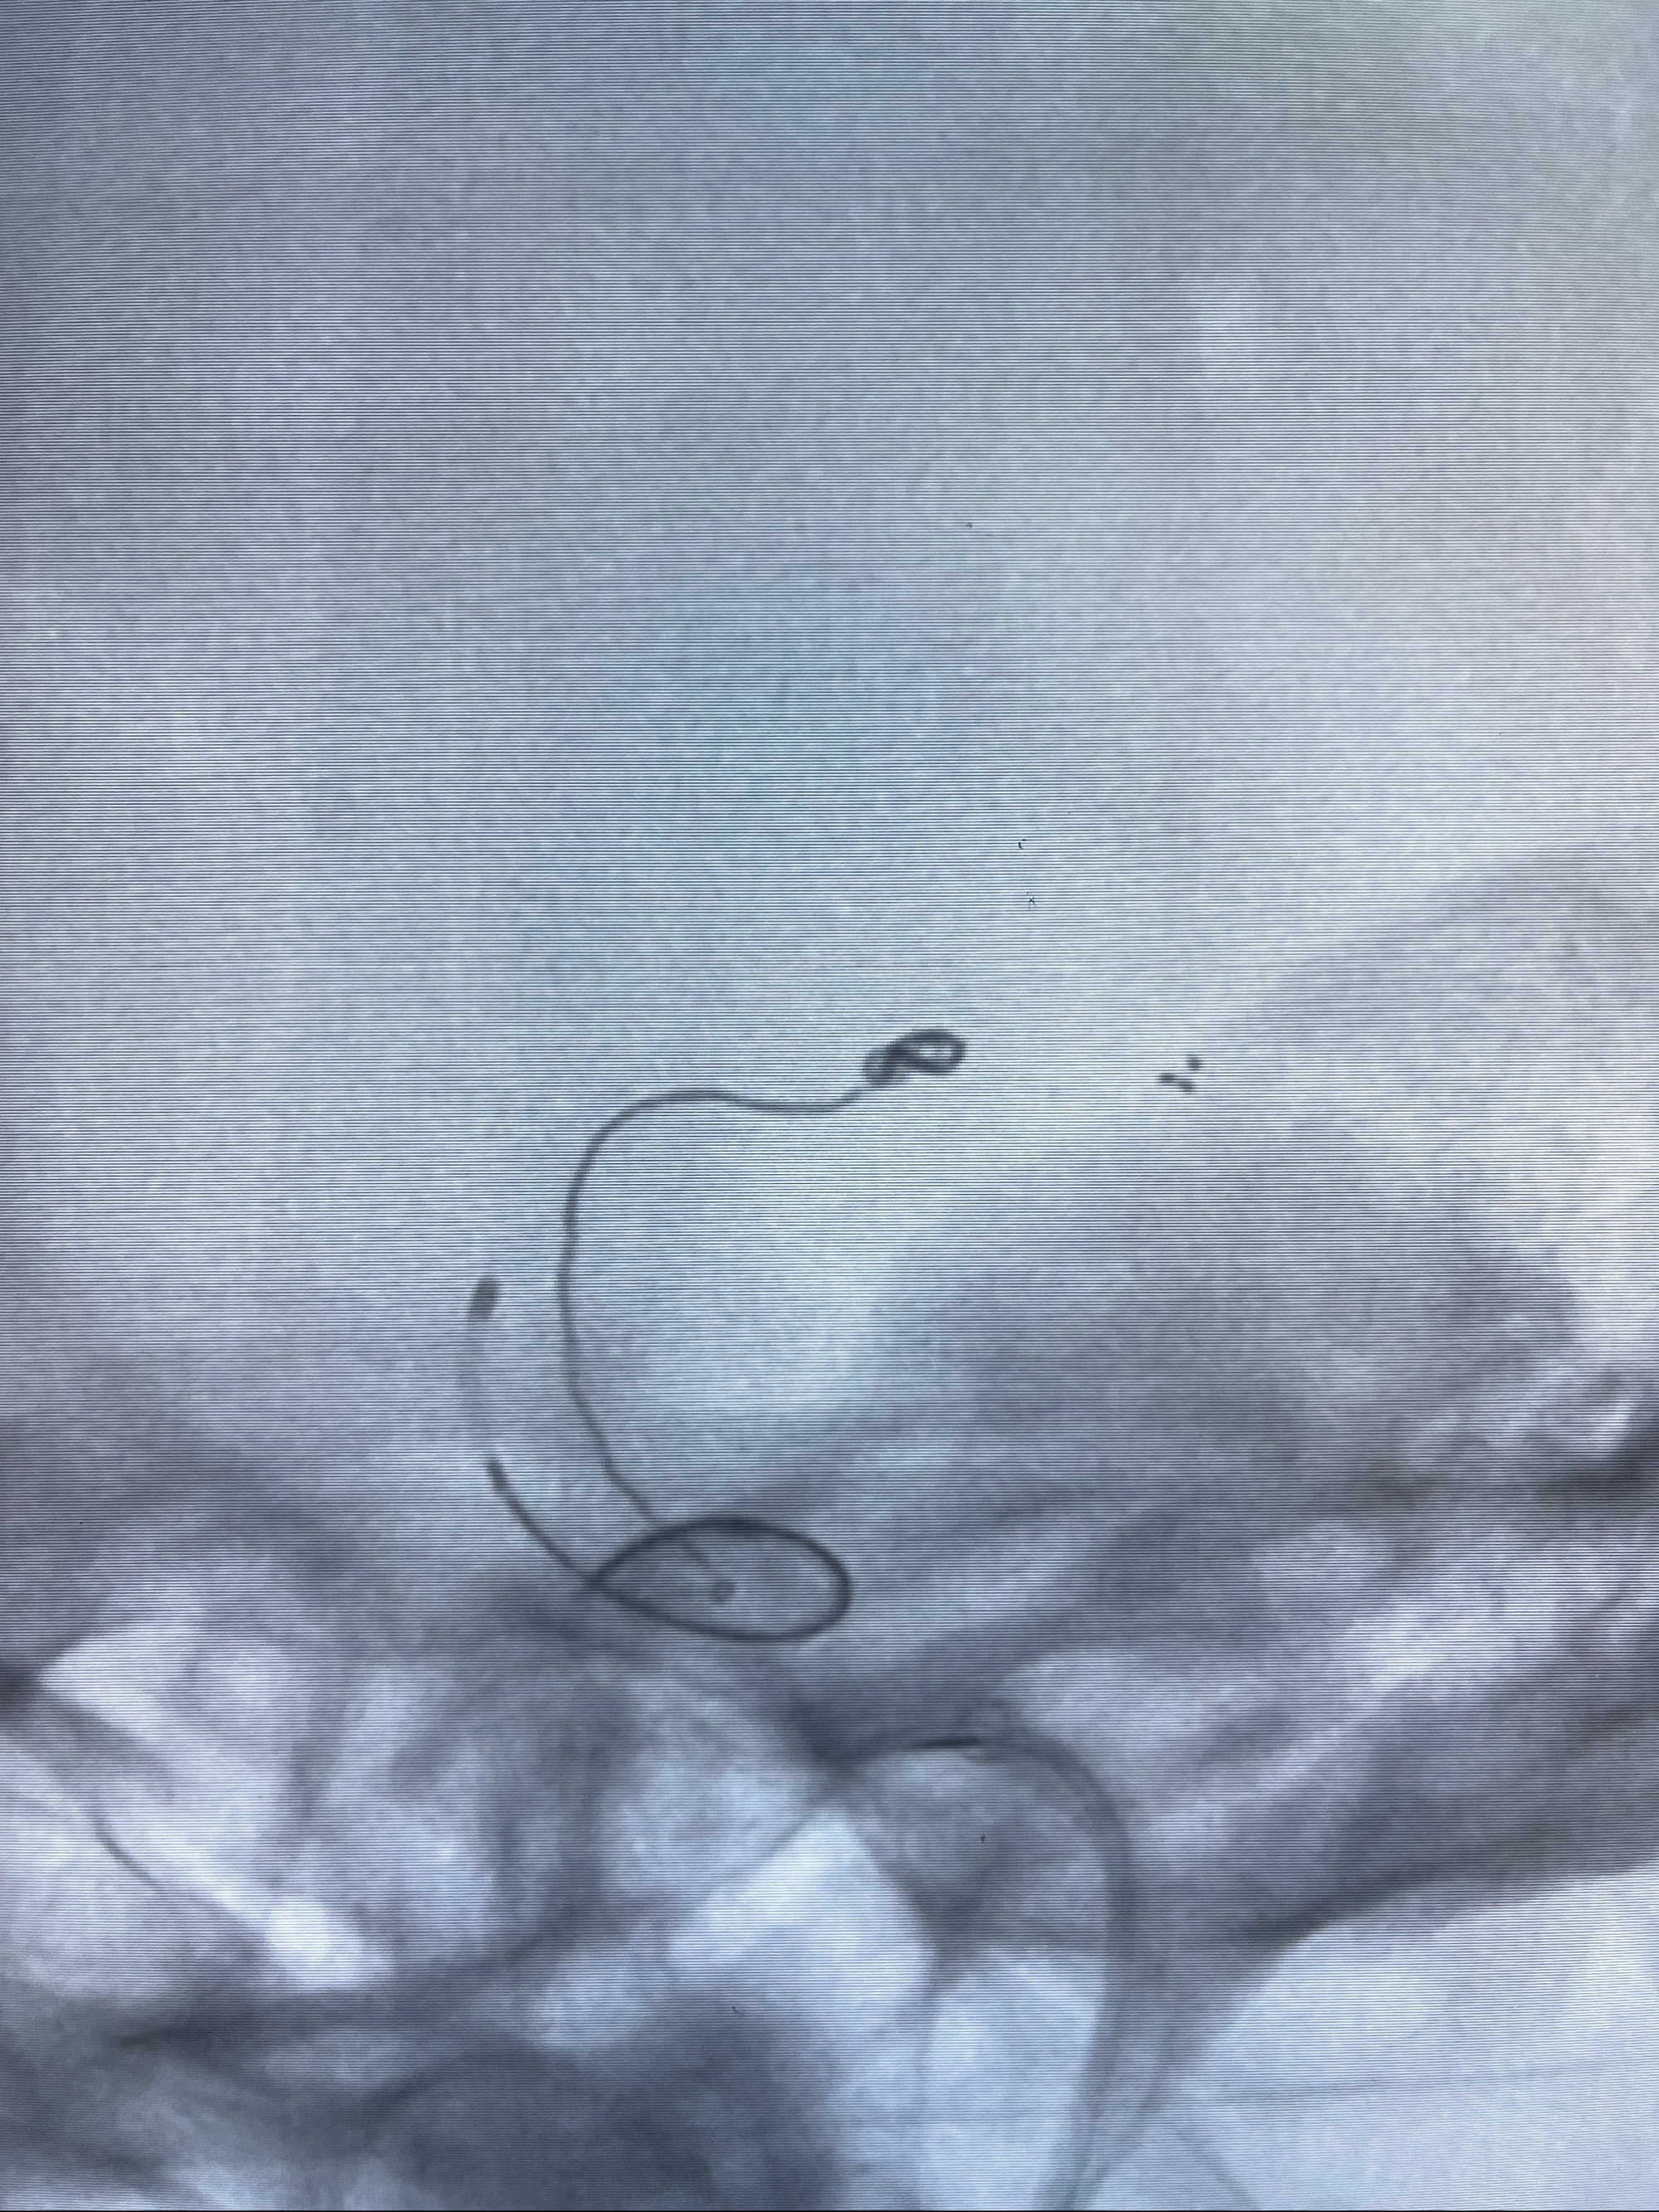

2023-08-14DSA:

左侧大脑中动脉动脉瘤,约2.6-2.8-3.4-2mm大小(瘤颈部、瘤体部、瘤高)

治疗策略:

1.左侧大脑中动脉动脉瘤,约2.6-2.8-3.4-2mm大小(瘤颈部、瘤体部、瘤高)

2.外科手术夹闭or介入支架辅助栓塞